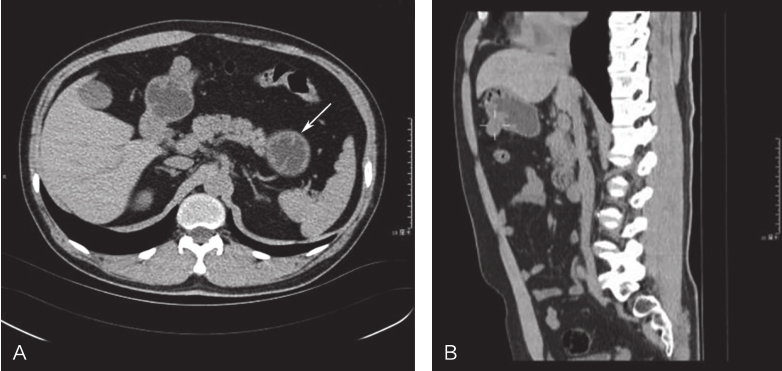

全腹部三维CT:①胃腔充盈一般,胃底大弯侧可见一软组织密度结节影向腔外突出,直径约1.5cm,考虑胃肠间质瘤;②肝脏大小及形态可,未见明显转移灶;③余腹腔未见明显转移灶(图1)。

图1 腹部CT提示胃底大弯侧软组织密度影

A.横断位;B.矢状位